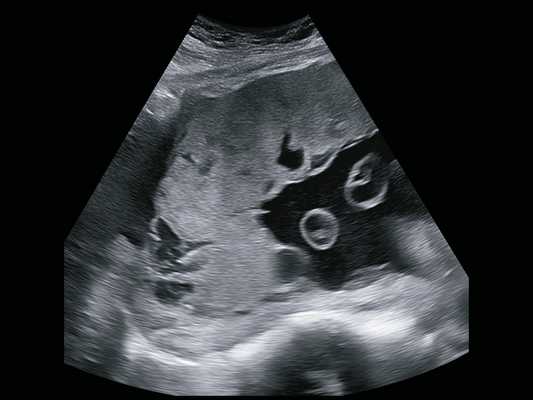

По данным УЗИ тип хориальности необходимо определять до 14 недель беременности.

Признаки ФФТС по данным УЗИ:

- Разность количества околоплодных вод у плодов (многоводие/маловодие)

- Различие размеров мочевого пузыря (малые размеры/отсутствие у плода донора с маловодием и большие размеры мочевого пузыря с многоводием у плода рецепиента)

- Водянка, асцит одного из плодов

- Различие массы плодов (более 20%). Опасность представляет, если разница в массе более 25-30%

Самый ранний срок, на котором можно разглядеть с помощью трансвагинального УЗИ плодное яйцо в полости матки - это 30-й день гестации, или 4-5 акушерских недель беременности. Уровень ХГЧ крови при этом должен быть не менее 1000 мЕд/мл. В это время ещё не видно ни эмбриона, ни желточного мешка. При визуализации двух плодных яиц можно утверждать, что это дихориальная многоплодная беременность. При визуализации одного плодного яйца можно утверждать, что это монохориальная беременность. Но на этом сроке мы ещё не можем сказать сколько эмбрионов находится в каждом плодном яйце. Кроме того, во время однократного УЗИ мы ещё не можем сказать, прогрессирует ли данная беременность, так как у эмбриона ещё нет сердцебиения. Средний внутренний диаметр (СВД) плодного яйца на этом сроке 2-10 мм.

Нормальные размеры желточного мешка 2-6 мм. Если в плодном яйце визуализируются два желточных мешка, значит это монохориальная многоплодная беременность. Но если внутри плодного яйца виден один желточный мешок, а эмбрион ещё отчётливо не визуализируется, то это всё ещё может оказаться монохориальная моноамниотическая двойня.

В случае монохориальной двойни ещё не видно амниотических оболочек и при наличии двух желточных мешков всё ещё нельзя сказать является ли данная беременность моно или диамниотической. Если плодное яйцо содержит два желточных мешка и два плода с наличием сердечной активности, в последующем количество амниотических полостей может быть больше, чем количество плацент (монохориальная диамниотическая) или одинаковым (монохориальная моноамниотическая). В этом случае точно определить амниональность возможно после 8 недель, когда амниотические оболочки начинают четко визуализироваться.

Случай острого развития синдрома анемии-полицитемии (TAPS) у монохориальной диамниотической двойни с синдромом селективной задержки роста плода (sIUGR)

По данным ISUOG, в последние десятилетия отмечено увеличение более чем на 70% случаев рождения двоен [1]. Это связано с широким внедрением вспомогательных репродуктивных технологий, отсроченным поздним зачатием, использованием противозачаточных препаратов.

По типу хориальности различают дихориальные и монохориальные двойни, причем 2/3 из них составляют дихориальные двойни.

Каждый плод из дихориальной двойни имеет собственную плаценту, свое отдельное сосудистое русло, и каждый развивается по своему сценарию, общим для них является состояние матери, которое, естественно, отражается на состоянии плодов.

Монохориальные двойни имеют одну общую плаценту. Практически в 100% случаев в общей плаценте имеются многочисленные сосудистые анастомозы, связывающие напрямую системы кровообращения обоих плодов. Плацентарные анастомозы бывают артерио -артериальные (АА), вено-венозные (ВВ) и артериовенозные (АВ) [2]. Все эти анастомозы могут располагаться и на поверхности плаценты, и в глубине. И если АА- и ВВ-анастомозы в большинстве случаев скомпенсированы, то АВ-анастомозы, где кровь из артерий одного плода дренируется напрямую в вены другого плода, являются причиной многочисленных осложнений.

По статистике, течение беременности при монохориальных двойнях осложняется в 10-15% случаев фето-фетальными трансфузионными синдромами (ФФТС) разной степени тяжести 5, причем клинические проявления ФФТС зависят от наличия именно АВ-анастомозов, их количества и размеров. Классический ФФТС диагностируется обычно на сроках от 16 до 26 нед и характеризуется наличием маловодия, максимальный вертикальный карман (МВК) менее 2 см у плода-донора, и многоводием, МВК более 8 см у плода-реципиента. Практически одновременно с этим первым признаком ФФТС при ультразвуковом исследовании (УЗИ) выявляется второй признак: у плода-донора мочевой пузырь или не визуализируется, или бывает значимо маленьким, а у реципиента - переполнен, или значимо большой. Эта самая частая форма ФФТС в настоящее время называется синдромом олигурии-полиурии (TOPS), связана с наличием крупных АВ-анастомозов на поверхности плаценты, приводящих к гиперволемии плода-реципиента и гиповолемии плода-донора. При своевременной ультразвуковой диагностике эта форма поддается антенатальной коррекции фетоскопической лазерной коагуляцией АВ-анастомозов.

При наличии глубоких АВ-анастомозов малого диаметра (до 1 мм) и в отсутствие компенсирующих АА-анастомозов в 3-5% случаев у монохориальной двойни может развиваться еще одна форма ФФТС - синдром анемии-полицитемии (TAPS), когда по мельчайшим анастомозам происходит хроническое медленное кровотечение от донора к реципиенту [6]. При УЗИ количество околоплодных вод может быть приблизительно одинаково нормальным, и заподозрить TAPS можно, если обратить внимание на разницу в толщине и эхогенности территорий плацент донора и реципиента. При измерении пиковой систолической скорости (ПСС) в средней мозговой артерии (СМА) каждого плода подтверждается, что у плода с признаками анемии с ПСС выше 1,5 МоМ территория плаценты утолщена, эхогенность ее повышена, а у реципиента с признаками полицитемии с ПСС ниже 1,0 МоМ территория плаценты обычной толщины и низкой эхогенности. В случае ФФТС в виде TAPS в отличие от TOPS существующие методы пренатального лечения не так эффективны, так как мелкие глубокие АВ-анастомозы практически не видны при фетоскопии. Некоторые специалисты проводят полную лазерную дихорионизацию плаценты по сосудистому руслу с предварительной амниоинфузией. Методом выбора является внутриутробная гемотрансфузия плоду-донору, однако она эффективна только в отсутствие значимо крупных анастомозов, усугубляющих полицитемию плода-реципиента. Таким образом, эффективность однократной гемотрансфузии плоду-донору имеет и лечебное, и диагностическое значение. В противном случае некоторые специалисты проводят обменные гемотрансфузии с возмещением реципиенту объема изъятой крови физиологическим раствором [7]. Так как в большинстве случаев TAPS возникает после 26 нед, все мероприятия направлены на продление беременности с целью достижения периода жизнеспособности плодов.

Синдром селективной задержки внутриутробного роста

Синдром селективной задержки внутриутробного роста (сЗВУР) выражается в отставании в росте одного из плодов и характеризуется дискордантностью фетометрических показателей двух плодов более чем на 25% и высчитывается по формуле:

При синдроме сЗВУР у монохориальной двойни при идентичном генном и хромосомном наборе может быть катастрофическая разница по площади принадлежащих плодам плацентарных территорий с аномальным развитием ворсин и сосудистого русла плацентарной ткани у плода с сЗВУР (рис. 1).

При терминальной плацентарной недостаточности происходит гибель меньшего плода, которая в большинстве случаев влечет за собой гибель нормального плода. Объясняется это наличием сосудистых анастомозов (АА и ВВ) в одной общей плаценте, но в отличие от ФФТС плацентарные анастомозы здесь играют положительную роль, долгое время компенсируя и поддерживая жизнь плода с маленькой плацентарной территорией (рис. 2).

УЗИ при многоплодной беременности

Многоплодная беременность считается беременностью высокого риска различных осложнений для матери и плодов, так как организм женщины больше рассчитан на вынашивание одного плода. Поэтому при многоплодной беременности необходимо более часто проводить УЗИ и наблюдать за ростом и развитием плодов.

Есть несколько типов двоен - в зависимости от количества плацент и оболочек.

Монохориальная диамниотическая двойня - возникает при разделении оплодотворенной яйцеклетки на две части. При этом у плодов имеется одна общая плацента и собственное околоплодное пространство. Плоды всегда одного пола и полностью генетически идентичны. Наличие единой плаценты может приводить к развитию специфических осложнений, связанных с тем, что сосуды в этой плаценте могут соединять системы кровообращения обоих плодов. При этом один плод получает некоторое количество крови от другого плода, и они оба страдают от этого: у одного есть избыток крови, что приводит к повышенной нагрузке на его сердце; второй получает недостаточное количество крови, кислорода и питательных веществ, и начинает расти медленнее, в результате чего у него формируется задержка внутриутробного развития. Такое осложнение называется фето-фетальный трансфузионный синдром, и без своевременного лечения может привести к гибели одного или обоих плодов. Для того, чтобы не пропустить это осложнение, необходимо делать УЗИ в 11-13 недель (как при одноплодной беременности), в 16, 18, 20, 22, 24, 26, 28 недель беременности. Если выявляются признаки фето-фетального синдрома, УЗИ нужно выполнять еще чаще - 1 раз в неделю. Если до 28 недель беременности нет никаких признаков этого синдрома, то в дальнейшем его развитие крайне маловероятно, и УЗИ можно выполнять 1 раз в 4 недели - как при дихориальной двойне.